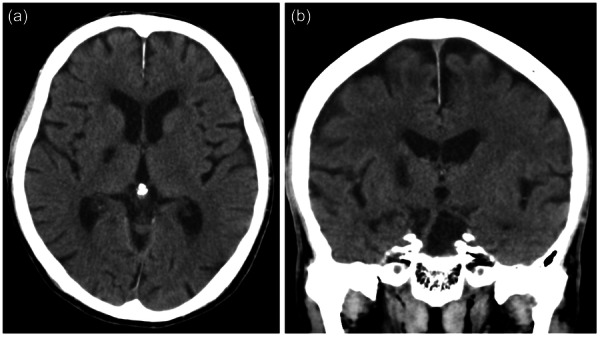

Case presentation: The patient, a retired man in his 70s diagnosed with AD, displayed OCD symptoms following donepezil initiation, exacerbating post-stroke-specifically, a cerebral infarction in the right posterior limb of the internal capsule. Remarkably, the symptoms abated upon discontinuation of donepezil.